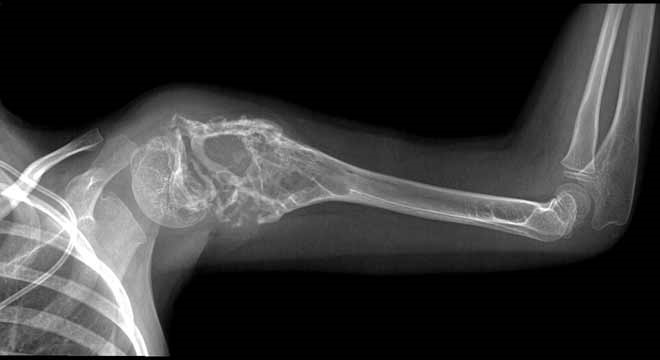

رادیوگرافی و سی تی اسکن

در این روش با کمک سی تی اسکن و رادیوگرافی وجود توده در استخوان مشخص می شود. برای تشخیص سرطان در بافتهای نرم بدن مانند ریه و غدد لنفاوی، پزشک یک مایع حاجب را به بیمار می دهد و بیمار پس از نوشیدن آن، در دستگاه سی تی اسکن قرار می گیرد و به این ترتیب، وجود توده ورشد سلول سرطانی تشخیص داده میشود.

🎗 سارکوم استخوان یا استئوسارکوم شایع ترین سرطان اولیه در استخوان

سارکوم استخوان

سارکوم استخوان یک سرطان محسوب می شود که در استخوان شروع می گردد. گاهی اوقات تمامی انواع سرطان استخوان را یک سارکوم نامگذاری می کند، درحالیکه سارکوم تنها نوعی سرطان استخوان می باشد.